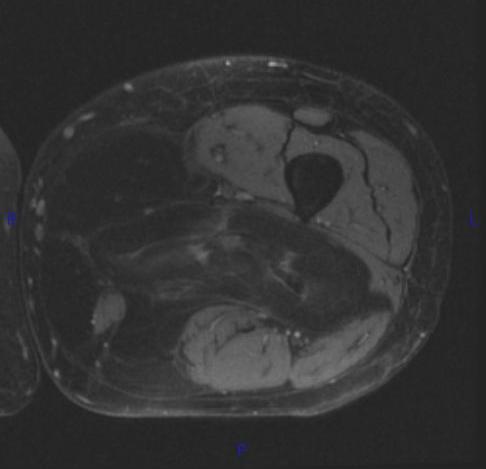

MRI (Fig. 1, 2, 3 and 4)

• Large encapsulated lipomatous mass. (Fig. 1, 2, 3 and 4)

• Nonadipose components; prominent thick septa and focal nodular regions usually less than 2 cm in size. (Fig. 3)

Fig. 2-4 MRI: Coronal T2-weighted fat suppressed (Fig. 2) and Axial T2-weighted FS (Fig. 3) shows low intensity signal isointense with fat. Adypocitic lesion with fatty signal is located in the posterior and medial compartment of the thigh. Thickened septa and nodularity enhances on post contrast images. (Fig. 4)